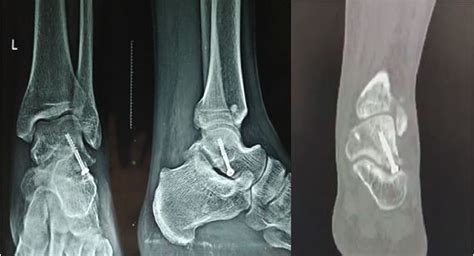

• Imaging Tests: Imaging tests, such as X-rays, MRI, or CT scans, are used to visualize the bone and cartilage within the ankle joint. These tests can help identify the location and extent of the lesion.

Imaging tests are particularly important in diagnosing Osteochondritis Dissecans Ankle, as they can provide detailed information about the condition of the bone and cartilage.